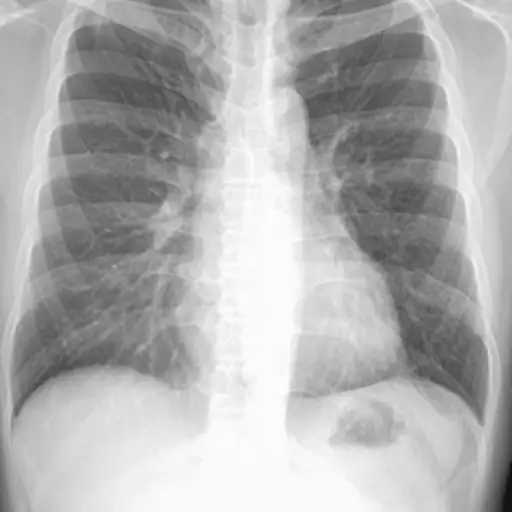

CT扫描

也被称为CAT扫描或计算机断层扫描,这一系列x光用于提供肺部的详细视图,包括任何可疑的肿块。对于那些可能患有非小细胞肺癌的患者,胸部或胸部CT扫描通常覆盖肝脏、肾上腺和肺部,它不仅可以用来识别任何肿瘤的位置,还可以用来识别附近淋巴结是否存在癌症。